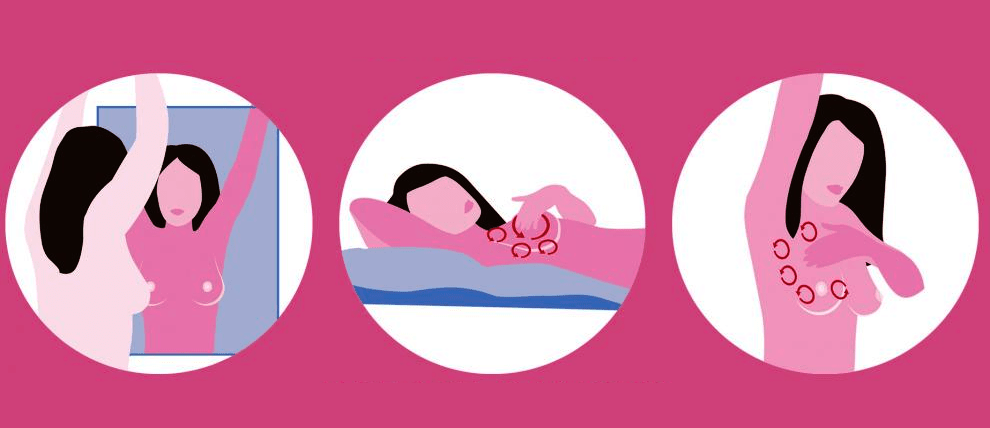

Self-examination pointers

Be regular in self-examination as it is important to catch any abnormal lumps or growths at the very initial stage itself.

- Visual – Stand in front of the mirror to see whether both breasts are symmetrical. Is there any puckering? Has the size changed? Does the areola look any different? Any dimpling?

- Physical – Palpate your breasts from base, sides to the nipples to carefully feel for any lumps, any abnormal hardening within the tissue.

- Discharge – Squeeze from the base of the breast, around the areola to the tip of the nipple to see if there is any kind of discharge.

- Armpits – Check your armpits for any lumps or nodes. Breast cancer does not always develop in the breast; it can also grow in the nodes.